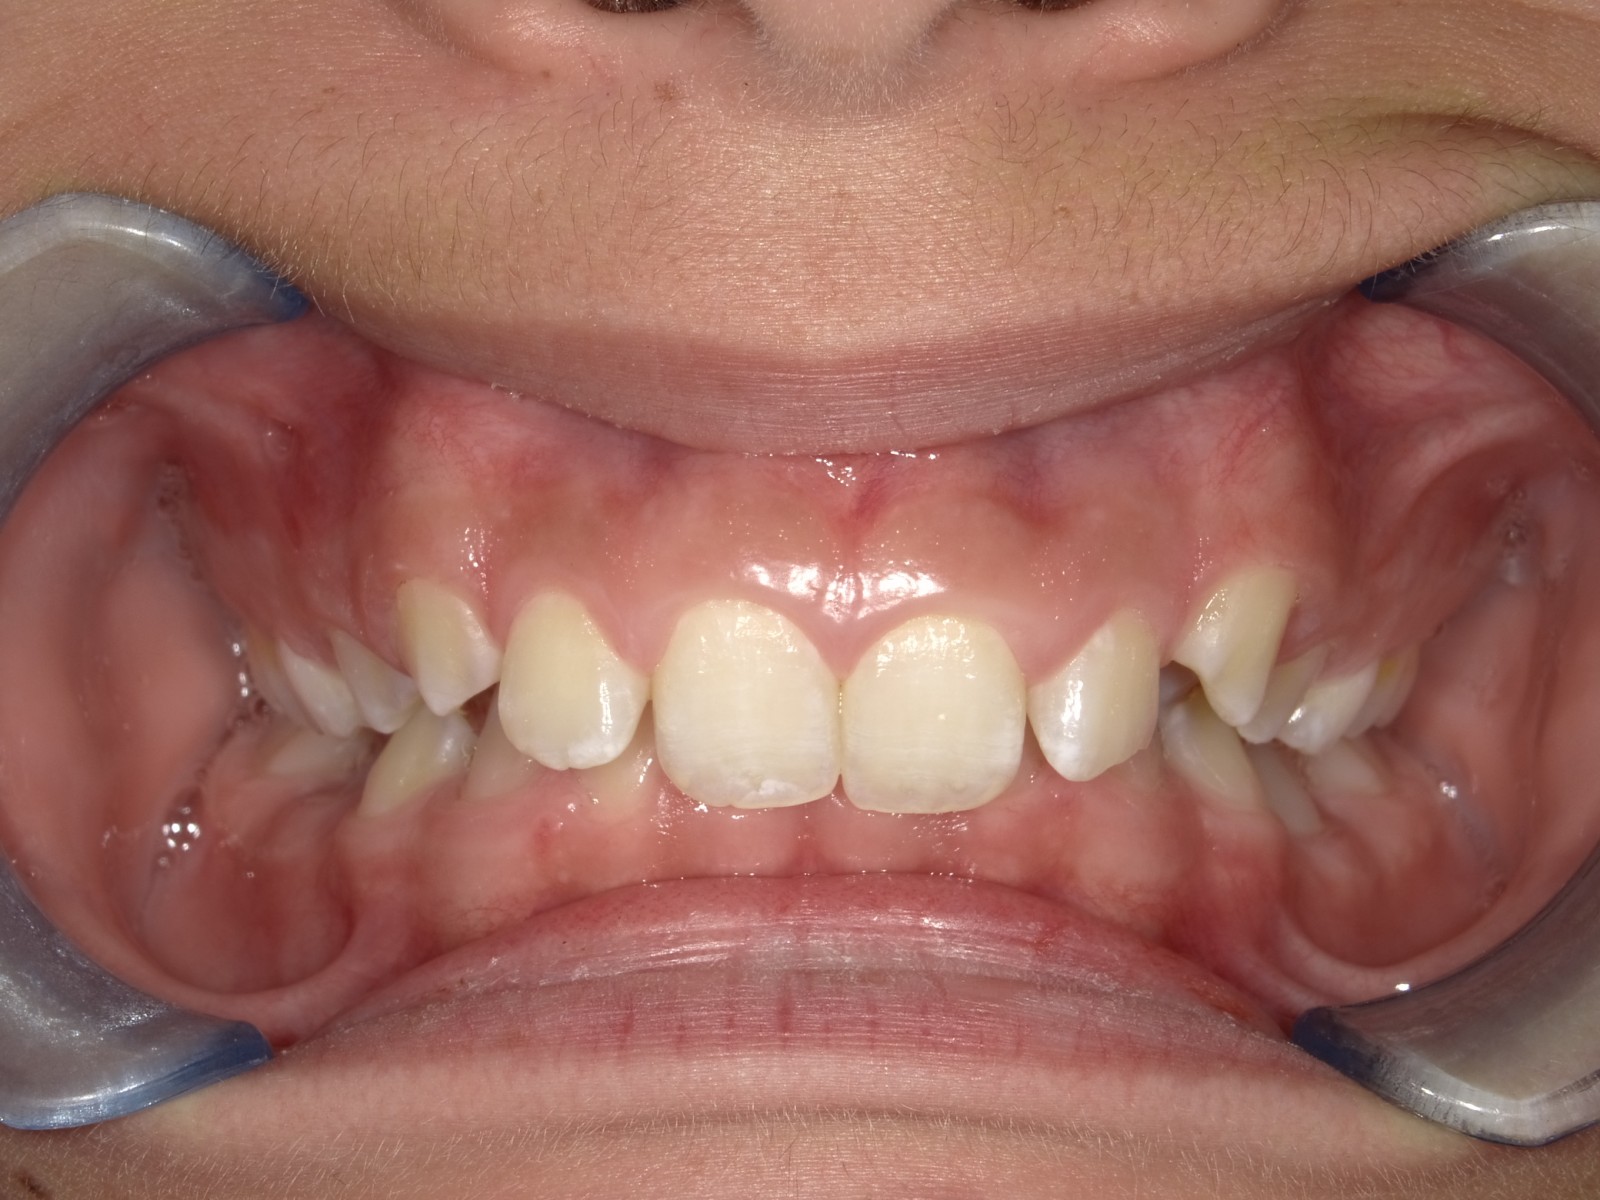

7-12 maand Distalizers